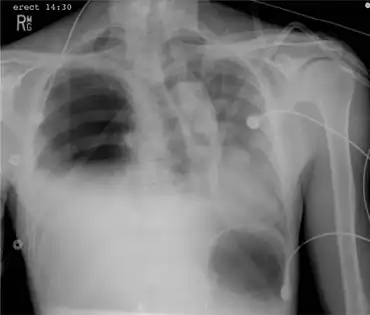

Portable chest x-ray demonstrating a right-sided tension hemopneumothorax

Hemopneumothorax, or haemopneumothorax, is the condition of having air in the chest cavity (pneumothorax) and blood in the chest cavity (hemothorax). A hemothorax, pneumothorax, or the combination of both can occur due to an injury to the lung or chest.[1]